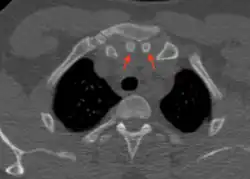

Episternal ossicles

Episternal ossicles (or suprasternal ossicles) are small bones that are sometimes present at the upper end of the chest bone. The prevalence of these ossicles is around 1.5%.[1]

The episternal ossicles are oval-shaped bones that are occasionally found at the superior and posterior border of the manubrium. The episternal ossicles were first described by Cobb in 1937.[2] They may be present unilaterally or bilaterally.[3] Its size ranges from 2–15 mm depending on individuals.[4] These ossicles are asymptomatic and does not cause any harm, although it may be diagnosed as fracture, vascular ossification or calcified lymph nodes.